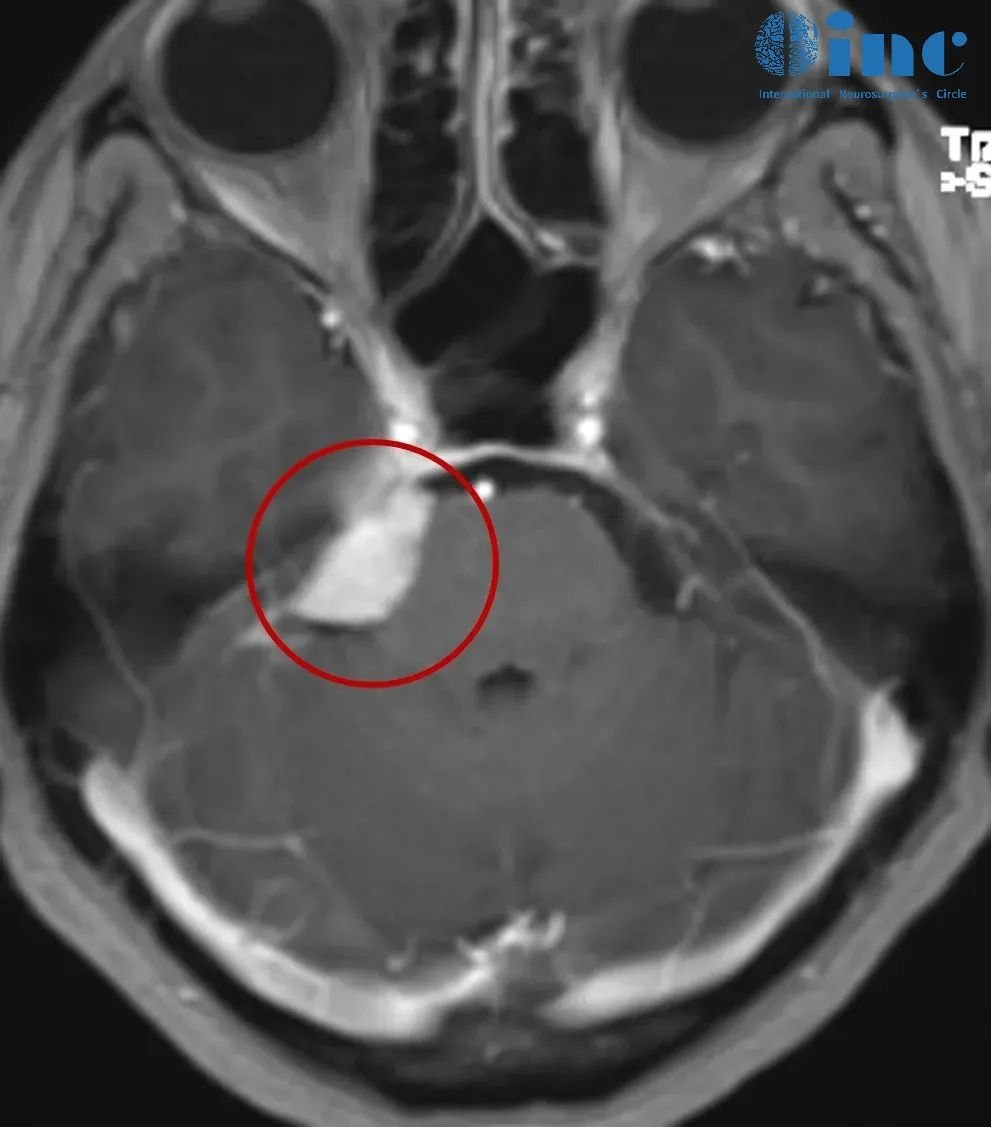

脑瘤4cm才被发现!当脑膜瘤“失控生长”压迫脑干,有多危险?

关于脑膜瘤,你了解多少? 绝大多数脑膜瘤为1级良性肿瘤,通常生长缓慢。这是多数患者对于脑膜瘤的初印象,当然这是事实。但是,脑膜瘤狡猾之处就在于它们通常在很长一段时间内静默性生...